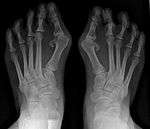

It is leaning of the first metatarsal bone away from the second metatarsal and towards the opposite foot (Fig. 1). As it leans over, its head sticks out to form the bunion bump and it also widens the forefoot to cause shoes feeling too tight. Thus when bunion pain becomes unmanageable, surgical correction is to narrow the forefoot by repositioning of the first metatarsal head back to its normal position. This can be done by osteotomy (bone-breaking), soft tissue (non-osteotomy) or fusion techniques.

Syndesmosis procedure addresses specifically the two fundamental problems of metatarsus primus varus deformity that gives rise to the bunion deformity. They are leaning and instability of the first metatarsal bone . Syndesmosis procedure uprights the leaning first metatarsal bone with strong binding sutures between it and the second metatarsal bone (Fig. 2) and then also stabilizes it uniquely by creating a fibrous connecting bridge between these two bones (Fig. 3,4). First metatarsal bone can be readily realigned is because by definition of the metatarsus primus varus deformity its first metatarsal is abnormally loose and mobile.